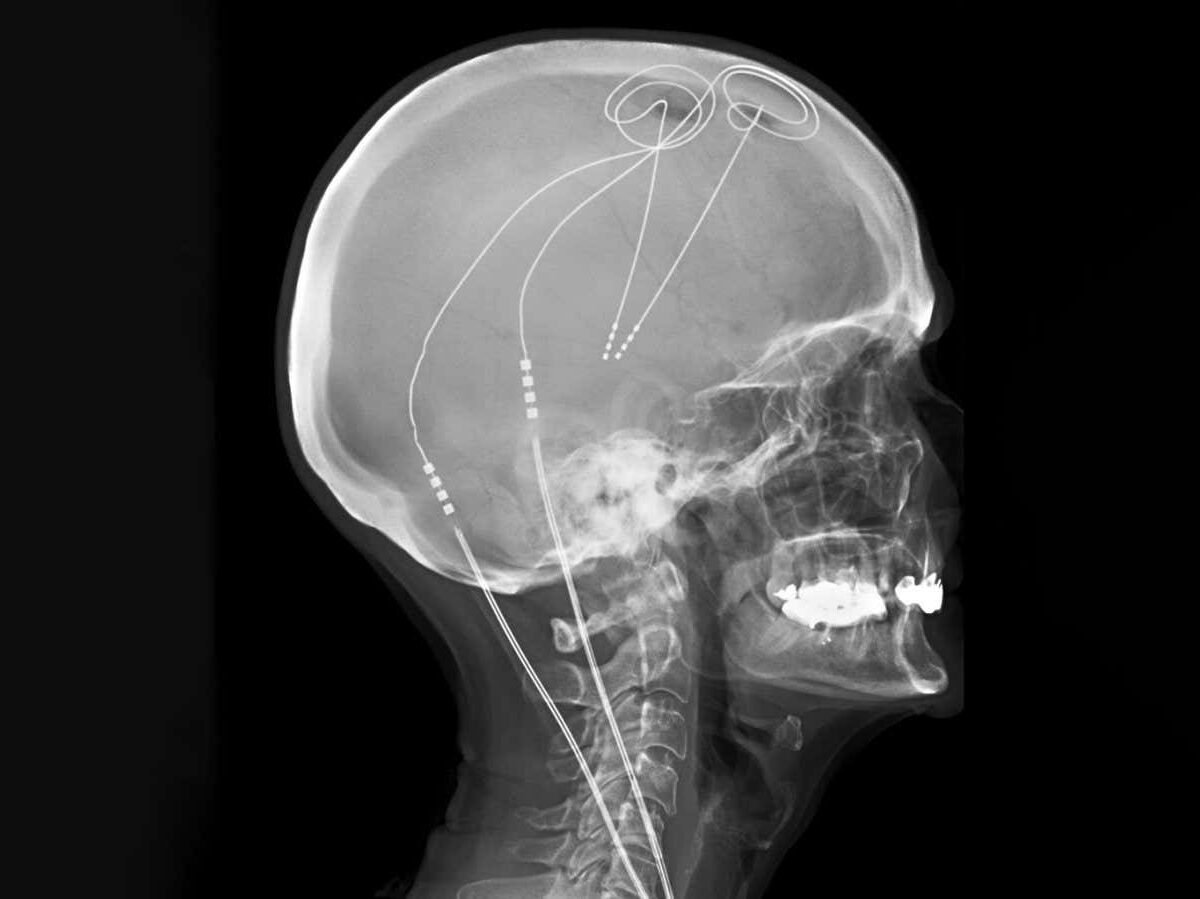

Deep brain stimulation is already used to treat Parkinson’s disease

Living Art Enterprises/SCIENCE PHOTO LIBRARY

Deep brain stimulation (DBS), which involves stimulating the brain using tiny electrodes, has shown promise but has inconsistent results. Traditionally, the same brain areas are targeted in a one-size-fits-all approach, despite evidence suggesting that pain arises from different circuits in different people.

The researchers next used machine learning to identify and distinguish between the electrical activity that occurred when the individuals experienced high or low levels of pain. They then implanted permanent DBS electrodes into each participant, which were personalised to monitor their brain activity and deliver optimal stimulation whenever pain-related activity was detected, and to deactivate when they were asleep.